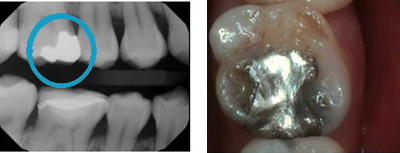

Amalgam Replacement

Replaces bad amalgam fillings with a tooth-like material. Restores the tooth to its original look. No red gum and trapping of food particles anymore. It provides a better appearance and better function.

Amalgam replacement with Cerec Onlay.

Creates long-lasting teeth by preserving more teeth structure in a biomimetic way!